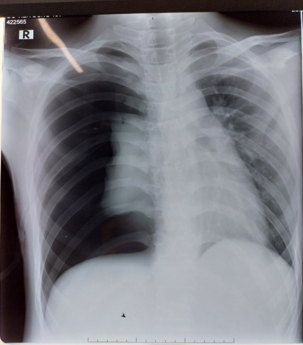

Bệnh nhân Đ.T.D 15 tuổi, tiền sử khoẻ mạnh, ngày 30/7/2023 vào viện vì đột ngột xuất hiện đau ngực phải, khó thở, ho khan được chẩn đoán Tràn khí màng phổi phải tự phát tiên phát, ngay trong ngày đã được xử trí ban đầu bằng dẫn lưu khí màng phổi tối thiểu, triệu chứng lâm sàng và hình ảnh trên phim Xquang lồng ngực ngực có cải thiện. 2 ngày sau thủ thuật được kẹp ống dẫn lưu màng phổi để kiểm tra, bệnh nhân đột ngột xuất hiện triệu chứng đau tức ngực phải nhiều, suy hô hấp, mạch nhanh, môi tím. Bệnh nhân được chỉ định chụp Xquang lồng ngực kiểm tra lại, kết quả cho thấy bệnh nhân bị tràn khí màng phổi phải tiếp diễn số lượng nhiều, xẹp phổi trái.

Hình ảnh Xquang tràn khí gây xẹp phổi P